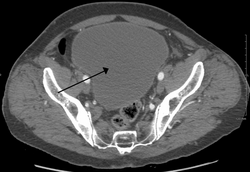

Urinary retention with greatly enlarged bladder as seen by CT scan.

Analysis of urine flow may aid in establishing the type of micturition (urination) abnormality. Common findings, determined by ultrasound of the bladder, include a slow rate of flow, intermittent flow, and a large amount of urine retained in the bladder after urination. A normal test result should be 20-25 mL/s peak flow rate. A post-void residual urine greater than 50 ml is a significant amount of urine and increases the potential for recurring urinary tract infections. In adults older than 60 years, 50-100 ml of residual urine may remain after each voiding because of the decreased contractility of the detrusor muscle.[4] In chronic retention, ultrasound of the bladder may show massive increase in bladder capacity (normal capacity is 400-600 ml).